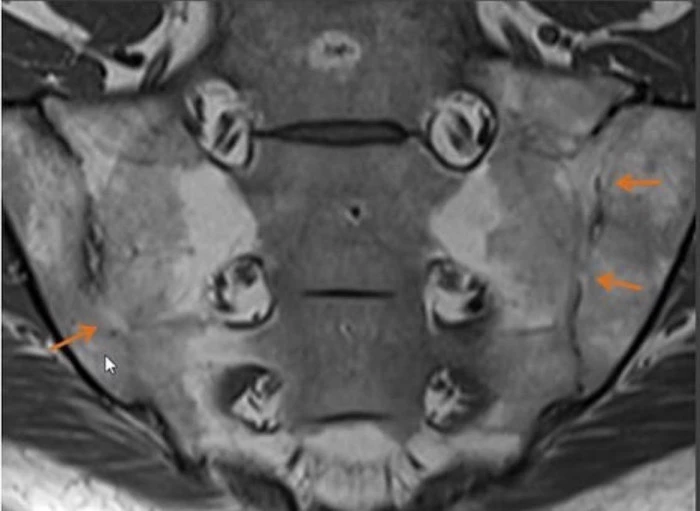

Магнитно-резонансная томография (МРТ) позвоночника, крестцово-подвздошных сочленений является диагностическим методом для раннего выявления воспаления в суставах позвоночника, его связок, определения наличия отека костного мозга, что позволяет судить о наличии острого или хронического воспаления.